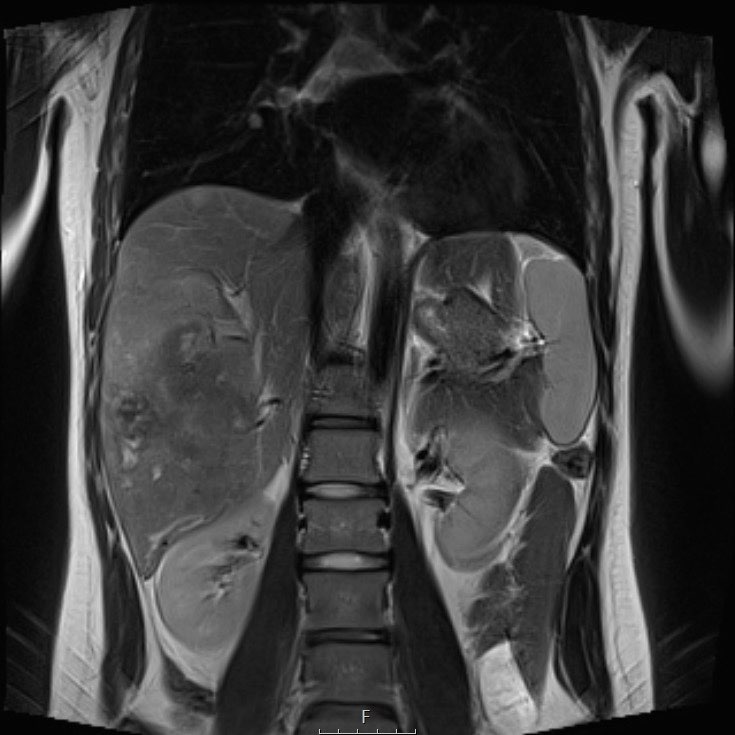

Ví dụ 1

Một bé gái 17 tuổi nhập viện với triệu chứng đau bụng vùng thượng vị. Siêu âm phát hiện một khối u gan lớn.

Trên MRI thấy khối u ở phân thùy gan 5 và 6 với các tổn thương vệ tinh ở phân thùy 7 và 8 (mũi tên). Có huyết khối u trong tĩnh mạch cửa phải (đầu mũi tên) và nhiều di căn phổi (*).